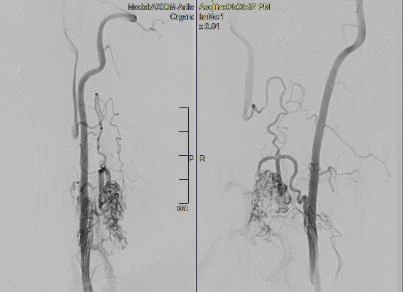

Hình ảnh mạch máu tủy của anh Đ. sau khi được can thiệp. Ảnh: BVCC |

Ca can thiệp tắc mạch cho anh Đ. thành công sau 2 giờ. Hiện tình trạng tay phải co rút, yếu nửa người bên trái đã hết hẳn. Anh Đ. đã tự đi đứng bình thường.